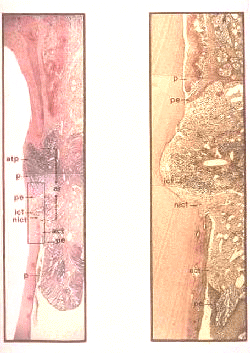

Ilustración esquemática de la anatomía de la destrucción periodontal en un solo diente arraigado. La magnitud de la destrucción periodontal varía en la superficie, con fronteras entre las partes normales y enfermas; la destrucción es muy irregular y se extienden  en todas las direcciones de la raíz.

Sección buco-lingual del periodonto en un diente molar de un perro con enfermedad periodontal naturalmente ocurriendo. El epitelio de unión se localiza hacia el cemento de la raíz. La terminación apical  del epitelio de unión desaparece exponiendo el tejido conjuntivo. La razón para esta variante de destrucción periodontal es la ocurrencia de las áreas vecinas de infección subgingival.